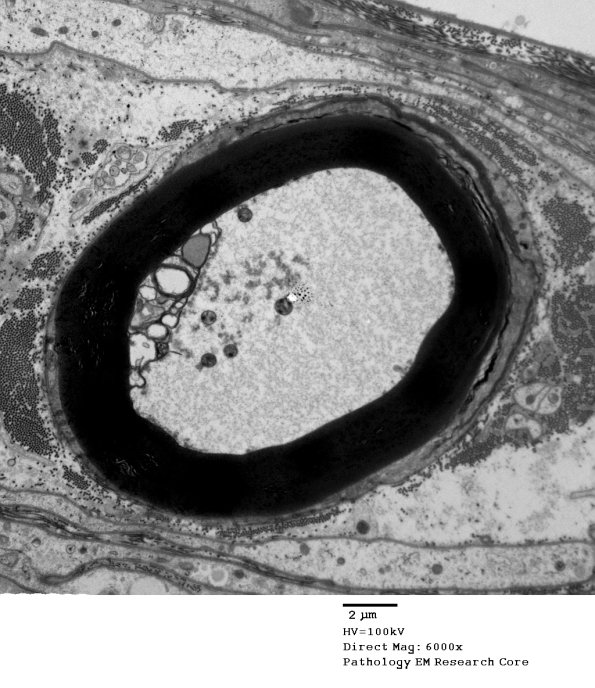

1D3,4 Cytoskeletal degeneration in the axoplasm is accompanied by degenerative changes in the adaxonal cytoplasm of the Schwann cell while the myelin structure is largely intact.